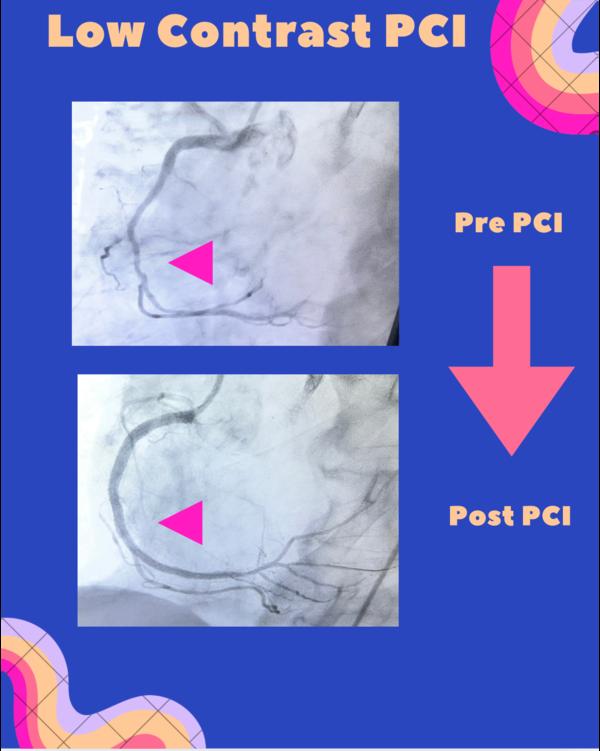

Image Gallery

Pictures That Speak